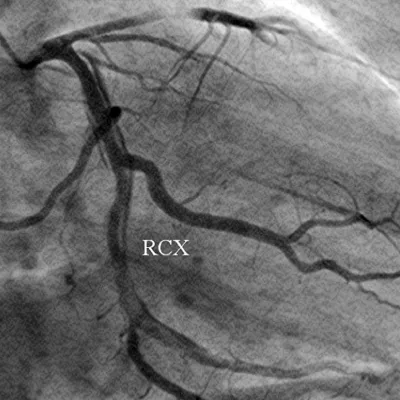

Figure 4: The left coronary artery shows an occlusion of the left anterior descending coronary artery (*) (left anterior oblique projection, RCX: ramus circumflexus).

Download Image

A 56-year-old obese man with a history of hypertension was admitted at night to the department of cardiology of our hospital because he had developed sudden onset right-sided thoracic pain with radiation into the right shoulder and right arm. He was sweating profusely and had massive nausea. The initially performed 12-lead ECG showed marked inferior ST segment elevations (Figure 1). Beside analgetics and oxygen, he was treated with aspirin, clopidogrel, heparin and the fibrin-specific thrombolytic tenecteplase. His symptoms resolved after 30 minutes. However, half an hour later, he developed left-sided thoracic pain, tachycardia, low blood pressure and the ECG signs of anterior ST-segment elevation myocardial infarction. The performed coronary angiography revealed a normal right coronary artery (Figure 2). The left coronary artery showed a long dissection of a large ramus circumflexus (RCX) (Figures 3,4). Additionally, the left anterior descending coronary artery (LAD) was occluded at about the mid-level (Figure 4, asterisk). Afterwards the left ventriculography revealed a reduced function and a Stanford type A aortic dissection with the intimal flap (Figure 5, arrows). Immediate patient transfer for emergency surgical intervention was arranged. During transport, ventricular fibrillation occurred, and he required endotracheal intubation as well as prolonged cardiopulmonary resuscitation. Unfortunately, he died due to a refractory cardiogenic shock during further transport.